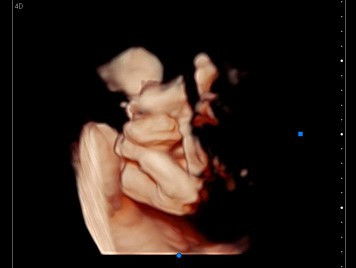

Haii moms.. Ada gk sih yg Kya aku walaupun aku hamil ke dua tpi rasa nya tetep sprti hamil anak pertama.. Stiap mau USG pasti excited bgt..♥️ #pregnant 24w3d BB janin 700gr Alhamdulillah masih di kategori kan aman sama dokter nya.. ♥️♥️ #masyallahtabarakallah